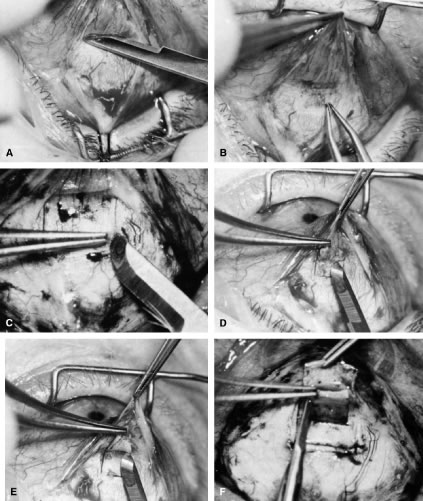

of a limbus-based flap appears unjustifiably difficult and risky.    Fig. 13. Limbus-based flap procedure. A. Conjunctiva is lifted away from the globe, stretched, and incised adjacent

to the superior rectus muscle bridle suture. B. The incision in the conjunctiva is extended nasally. C. The conjunctival incision is extended temporally. D. Tenon's capsule is lifted up, away from the globe, and incised with

the scissors held obliquely to avoid cutting into the underlying superior

rectus muscle. E. The incision in Tenon's capsule is spread bluntly. F. The superior rectus muscle can be seen through the buttonhole in Tenon's

capsule. Bleeding should be minimal; if it occurs, it should be

controlled promptly with cautery. G. Tenon's capsule is incised nasally and temporally. H. The connective tissue overlying the superior rectus muscle is seen easily

after Tenon's capsule has been incised. This tissue usually is

highly vascular in the area directly at the base of the superior rectus

muscle. I. Episclera is buttonholed approximately 4 mm posterior to the limbus, showing

the underlying sclera. J. One blade of the scissors is insinuated between the sclera and the episclera, and

the episclera is incised nasally. K. The episclera is incised temporally. The plane of the scissors is flush

with the sclera. L. Remaining adhesions between the episclera and sclera are dissected in

a semisharp fashion with the no. 67 Beaver blade, which is pushed at right

angles to the cutting axis. M. Tenon's capsule is closed in a separate layer with an 8-0 absorbable

suture. N. The superior edge of Tenon's capsule tends to retract up under the

lid. It can be hooked over the needle and pulled inferiorly. Sutures

are locked. O. After Tenon's capsule is closed, the needle is placed from the underneath

side to the superficial side of the conjunctiva and exteriorized

so that it can be used to close the conjunctiva. P. The conjunctiva is closed with closely spaced running, unlocked sutures. The

final suture is tied securely. Q. After the needle has passed through the tissue, it is lifted away from

the globe firmly. The underlying tissue is stretched. A blunt forceps

is used to grasp this underlying tissue firmly, as close to the needle

as possible. This maneuver will hold the needle firmly in place, permitting

the surgeon to release the end of the needle containing the suture

without having to change the position of the needle. R. The needle can be regrasped toward the cutting end so that it is held

in proper position for placement of the next suture. (Spaeth GL. Glaucoma surgery. In Spaeth GL (ed). Ophthalmic Surgery: Principles

and Practice. Philadelphia: WB Saunders, 1990.) Fig. 13. Limbus-based flap procedure. A. Conjunctiva is lifted away from the globe, stretched, and incised adjacent

to the superior rectus muscle bridle suture. B. The incision in the conjunctiva is extended nasally. C. The conjunctival incision is extended temporally. D. Tenon's capsule is lifted up, away from the globe, and incised with

the scissors held obliquely to avoid cutting into the underlying superior

rectus muscle. E. The incision in Tenon's capsule is spread bluntly. F. The superior rectus muscle can be seen through the buttonhole in Tenon's

capsule. Bleeding should be minimal; if it occurs, it should be

controlled promptly with cautery. G. Tenon's capsule is incised nasally and temporally. H. The connective tissue overlying the superior rectus muscle is seen easily

after Tenon's capsule has been incised. This tissue usually is

highly vascular in the area directly at the base of the superior rectus

muscle. I. Episclera is buttonholed approximately 4 mm posterior to the limbus, showing

the underlying sclera. J. One blade of the scissors is insinuated between the sclera and the episclera, and

the episclera is incised nasally. K. The episclera is incised temporally. The plane of the scissors is flush

with the sclera. L. Remaining adhesions between the episclera and sclera are dissected in

a semisharp fashion with the no. 67 Beaver blade, which is pushed at right

angles to the cutting axis. M. Tenon's capsule is closed in a separate layer with an 8-0 absorbable

suture. N. The superior edge of Tenon's capsule tends to retract up under the

lid. It can be hooked over the needle and pulled inferiorly. Sutures

are locked. O. After Tenon's capsule is closed, the needle is placed from the underneath

side to the superficial side of the conjunctiva and exteriorized

so that it can be used to close the conjunctiva. P. The conjunctiva is closed with closely spaced running, unlocked sutures. The

final suture is tied securely. Q. After the needle has passed through the tissue, it is lifted away from

the globe firmly. The underlying tissue is stretched. A blunt forceps

is used to grasp this underlying tissue firmly, as close to the needle

as possible. This maneuver will hold the needle firmly in place, permitting

the surgeon to release the end of the needle containing the suture

without having to change the position of the needle. R. The needle can be regrasped toward the cutting end so that it is held

in proper position for placement of the next suture. (Spaeth GL. Glaucoma surgery. In Spaeth GL (ed). Ophthalmic Surgery: Principles

and Practice. Philadelphia: WB Saunders, 1990.)